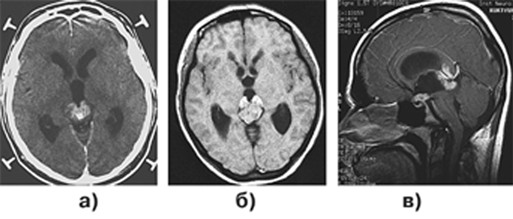

Диагноз устанавливается при МРТ и КТ, верифицируется стереотаксической биопсией. Для этих опухолей наиболее характерна симметричная инфильтрация задних отделов зрительных бугров в сочетании с центральным расположением петрификата, что дает характерную картину “бабочки” с расправленными крыльями. Этот рентгенологический признак наблюдается только при герминомах и не характерен для других опухолей (рис. 1).

Рисунок 1. Герминома шишковидной железы: